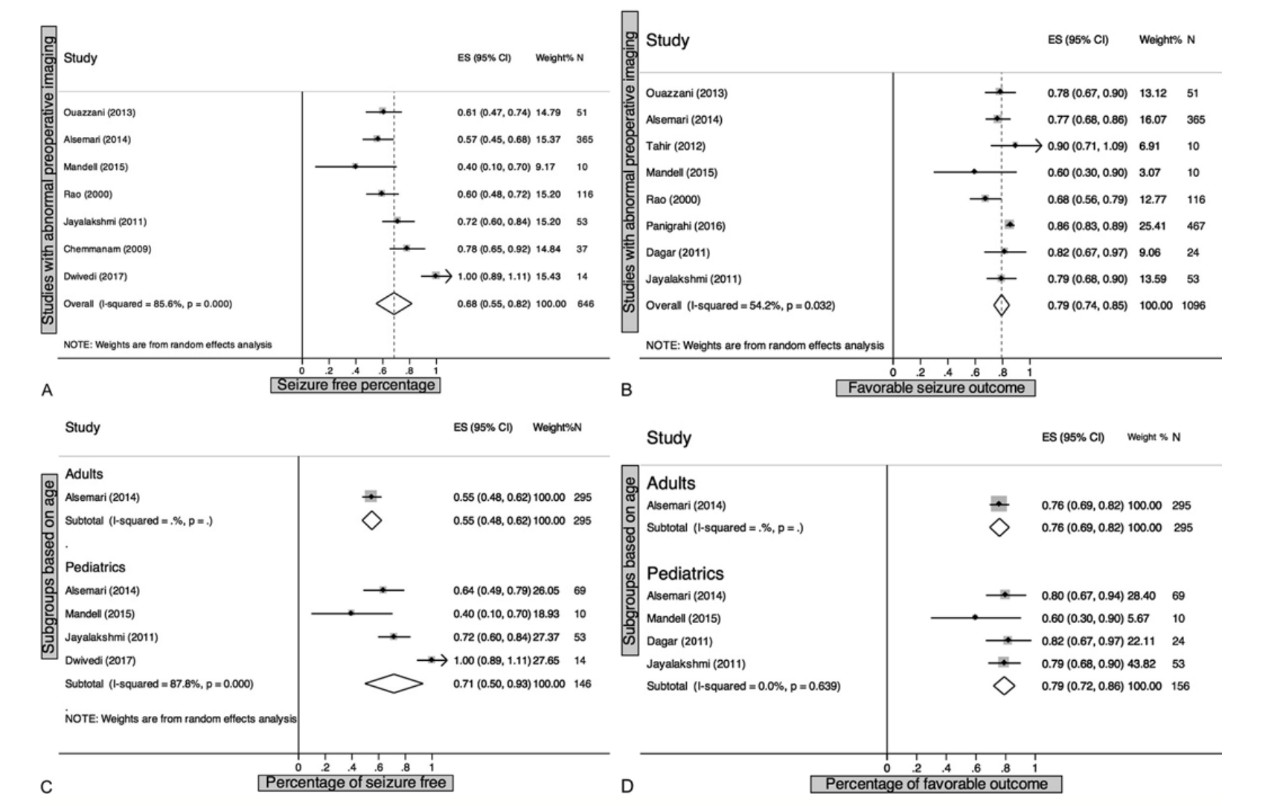

作者系统回顾了发展中国家进行癫痫手术的病例,共纳入了20项研究,其中16项来自亚洲。所有研究中,手术患者的平均年龄均小于30岁,癫痫的平均术前持续时间为3至16.1年。颞叶硬化占951例有手术病理中的437例,1773例手术中的1294例为ATL±AH。根据7项研究(646例),ATL±AH后的癫痫无发作率为68%(95%CI 55%–82%)。基于8项研究(1096例),癫痫无发作率为79%(95%CI 74%–85%)。结果表明:1)在发展中国家,有很多中心在开展癫痫手术;2)癫痫手术预后与发达国家一样好;3)手术是安全的。他们建议需要更多的支持,资源和资金,以保证药物难治性癫痫患者及时得到手术治疗。

图:前颞叶切除±杏仁核-海马切除(ATL±AH)治疗难治性癫痫的荟萃分析。